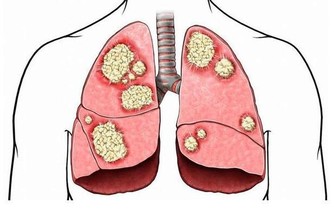

如果腸道裡面出現了腫瘤細胞,這些腫瘤細胞就會快速的繁殖,導致腸道的空間變窄,大便也因此會變細,尤其是直腸部位出現腫瘤細胞之後這種情況更加明顯。

所以,一旦發現自己的大便變得越來越細就要及時到醫院檢查治療,以免腸道完全阻塞之後無法順利排便。癌症進入晚期之後會大大的增加治療的難度,使生命受到嚴重的威脅。